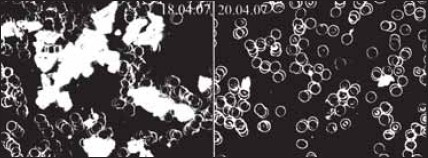

Повышенная нагрузка на гемоглобиновый буфер крови вызывает изменения реополиглютических свойств и характеристик крови, замедление кровотока, повышение агрегации (склеивания) эритроцитов, ослабление снабжения тканей кислородом. Это приводит к тому, что организм не получает в достаточном количестве питательных веществ, витаминов, кислорода, из клеток не выводятся шлаки. На рис. 16 ясно видны изменения крови, вызванные окислением организма.

Живая и мертвая вода – новейшее лекарство современности - i_020.jpg

Рис. 16. Слева – картина крови здорового человека. Справа – изменения крови при окислении организма. Фазово-контрастная микроскопия (Dunkelfeldmikroskopie). Источник: www.drada-fischer.de/dunkel.html